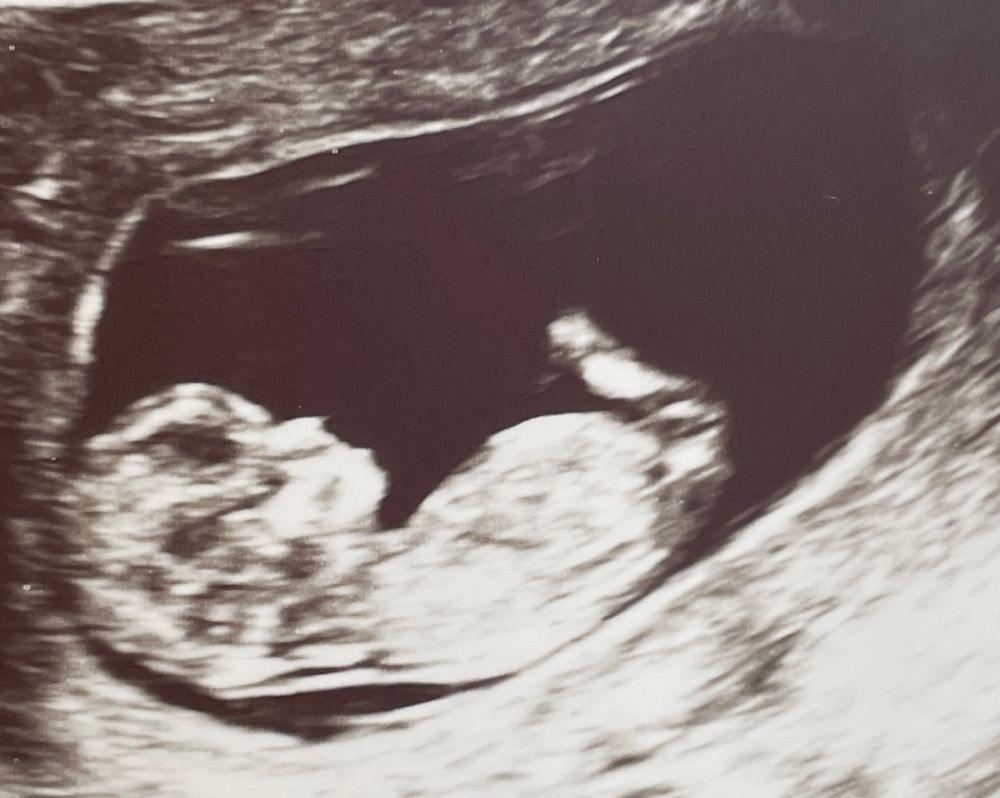

Так было на первом скрининге) мальчик